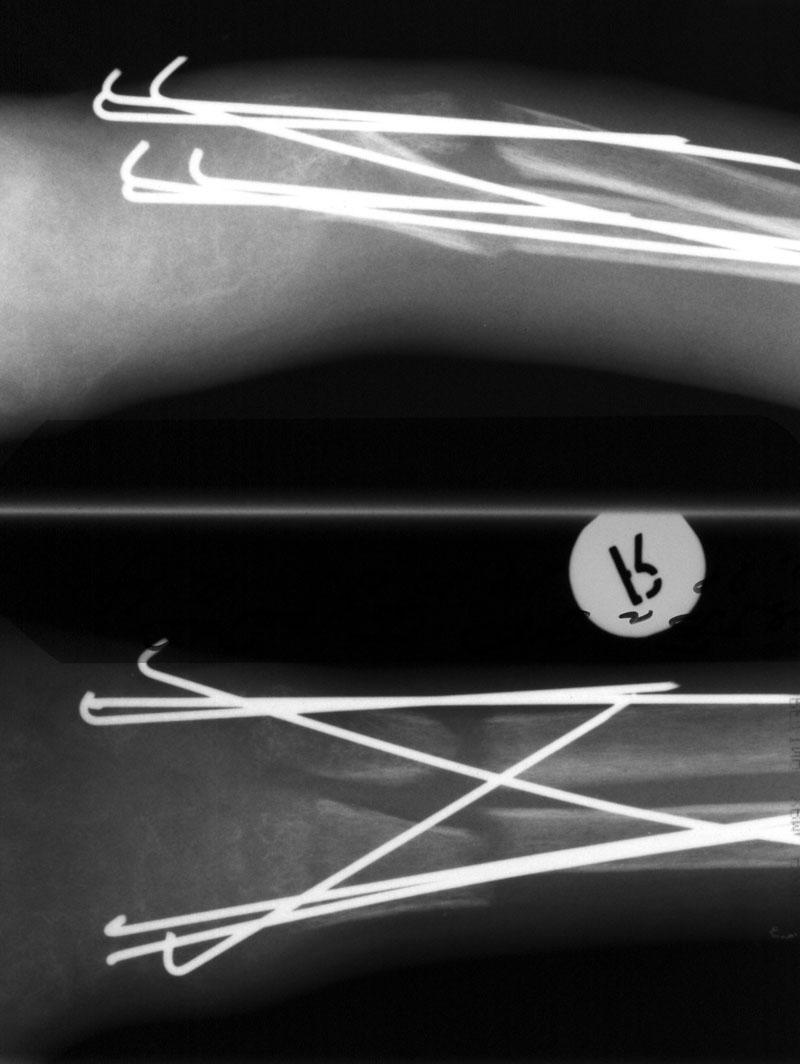

Выписка из амбулаторной карты пациента, 1980 г.р.Находится под наблюдением в поликлинике КНЦ РАН. Состоит на "Д" учёте по заболеваниям:Ювенильный идиопатический генерализованный остеопороз. Деформация грудной клетки за счёт множественных переломов грудины, рёбер. S-образный кифосколиоз грудного отдела позвоночника.Синдром гипофосфатемии неясного генеза. ВСД по кардиальному типу.Инвалид 1-й группы с детства. Последние 4 года не может передвигаться, возникают патологические переломы. Живёт в семье, материально-бытовые условия удовлетворительные.За последние 2 года состояние значительно ухудшилось - усилилась общая слабость, участились патологические переломы, которые не срастаются. Постоянно лежит в постели. Постоянный приём препаратов кальция и диеты с повышенным содержанием кальция, фосфора и белка эффекта не дают. С 11.07.2002 по 30.07.2002 г. лечился в травматологическом отделении АЦГБ с переломом костей правого предплечья со смещением. С 24.08.2002 по 08.09.2002 г. лечился в терапевтическом отделении по поводу острого бронхита с бронхоспастическим компонентом.На сегодняшний день статус. Состояние относительно удовлетворительное. В сознании. Положение вынужденное: сидя в инвалидном кресле, сам встать на ноги и передвигаться не может, туалет только с помощью родственников. Бледный, астеничный. Выраженная деформация грудной клетки, выраженный кифоз и сколиоз грудного отдела позвоночника. Экскурсия грудной клетки ограничена. Участие в акте дыхания вспомогательных межрёберных мышц. Пальпация грудной клетки безболезненна. Деформация всех крупных и мелких суставов за счёт увеличенных эпифизов. Деформация длинных трубчатых костей, мышцы рук и ног атрофичны. Температура - 36,8, ЧД - 29 в минуту. Дыхание жёсткое, проводится во все отделы. Слева от угла лопатки и в аксиллярной области влажные мелкопузырчатые хрипы, в межлопаточной области с обеих сторон свистящие хрипы. Пульс 90 ударов в минуту, ритмичный, симмитричный, слабого наполнения и напряжения. АД 120\80 мм рт. ст. Границы относительной сердечной тупости не расширены. Тоны сердца громкие, ритм правильный. Язык влажный, блестит. Живот при пальпации мягкий, не вздут, симметричный, участвует в акте дыхания, безболезненный. Печень по краю рёберной дуги. Стул регулярный, оформлен, без патологических примесей. Мочеиспускание свободное, безболезненное. Симптом Пастернацкого отрицателен с обеих сторон. Отёков нет.Анализ крови общий 26.08.2002: Hb-146 г\л, Эр.-4,8, ЦП-0,91, Лейк.-6,4, п.-4, с.-45, э.-5, м.-11, СОЭ-4 мм\ч.Анализ мочи общий 26.08.2002: Уд. вес-1025, белок-0,01, сахар-нет, лейк.-0-1 в поле зр., слизь+++, бактерии+.Анализ крови биохимический 26.08.2002: глюкоза-4,9, АЛТ-0,3, АСТ-0,5, биллирубин-11,9, креатинин-44,2, мочевина-3,8, СРБ (+).Анализ крови на микрореакцию - отрицательный.Флюрограмма за 2002: Резко выраженная деформация грудной клетки за счёт множественных переломов рёбер, грудины. Инфильтративных теней в лёгких не определяется. По сравнению с предыдущим исследованием от 01.12.2000 г. - ухудшение: нарастают деформация грудной клетки и позвоночника.ЭКГ за 2002 год: Синусовая тахикардия с ЧСС 88 в минуту. Отклонение ЭОС вправо. Признаки нарушения процессов реполяризации миокарда задней стенки левого желудочка. Повидимому, изменения ЭКГ обусловлены позиционными изменениями, возможно астеничным телосложением.Дополнительные методы исследования.Рентген правого предплечья (17.10.2002): Металлоостеосинтез по поводу перелома обеих костей правого предплечья в н\з: признаки репарации практически не определяются, сохраняется диастаз между отломками.Рентген правого предплечья (24.04.2003): Металлоостеосинтез по поводу перелома обеих костей правого предплечья в н\з: признаки репарации отсутствуют, формируются ложные суставы. Резко выраженный остеопороз.Рентген правого бедра (18.02.2003): Несросшийся перелом правого бедра на границе с\з и н\з со смещением отломков под углом открытым кнутри. Формирующийся ложный сустав. Выраженный остеопороз костей.Рентген правого бедра (24.04.2003): Угловое смещение отломков правого бедра увеличилось. Признаки репарации крайне вялые: по наружному краю отломков формируются замыкательные пластинки - ложный сустав. Выраженный остеопороз.

Так и выполнялось. Спицы стоят вот уже почти год, консолидации нет.

А чего собственно консервативным? Это к остеопорозу от бездействия приведет еще больше. Уж если взялись лечить диафизарный перелом, то лучше бы его было хорошо сопоставить и фиксировать, идеально закрыто стержнем. Можно и

аппаратом, используя спицы с упорами, проводимые на разных уровнях. А на примере предплечья здесь - и вроде что-то делали, а в то же время и

сопоставления хорошего нет, и фиксация нестабильная, и из-за пучков спиц этих функция мышц нарушена... То бишь все условия для форомирования ложного сустава.